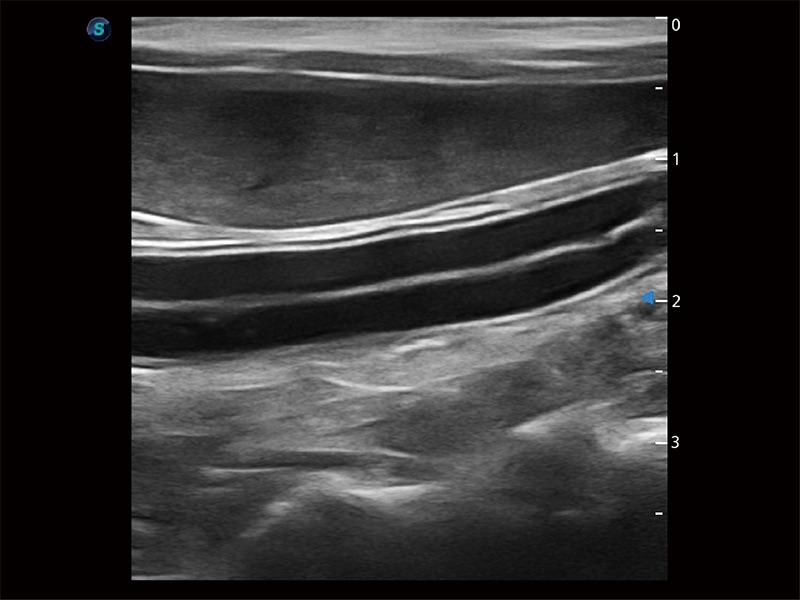

(犬)肠道

(猫)二尖瓣M型